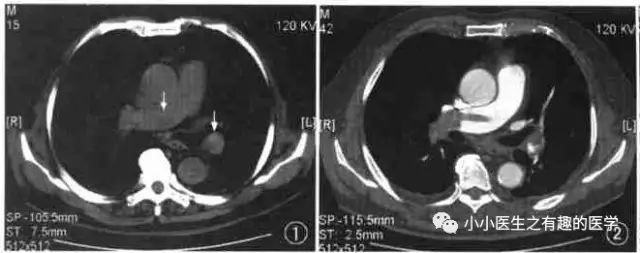

其实,我大中华也有医生用CT平扫发现可疑肺栓塞。

下面是上海交通大学的论文

↓↓↓

基本上看得到。